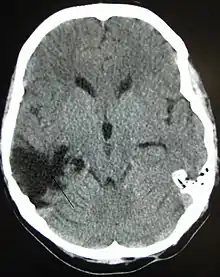

Hematomas, also focal lesions, are collections of blood in or around the brain that can result from hemorrhage.[11] Intracerebral hemorrhage, with bleeding in the brain tissue itself, is an intra-axial lesion. Extra-axial lesions include epidural hematoma, subdural hematoma, subarachnoid hemorrhage, and intraventricular hemorrhage.[38] Epidural hematoma involves bleeding into the area between the skull and the dura mater, the outermost of the three membranes surrounding the brain.[11] In subdural hematoma, bleeding occurs between the dura and the arachnoid mater.[23] Subarachnoid hemorrhage involves bleeding into the space between the arachnoid membrane and the pia mater.[23] Intraventricular hemorrhage occurs when there is bleeding in the ventricles.[38]

Prognosis differs depending on the severity and location of the lesion, and access to immediate, specialised acute management. Subarachnoid hemorrhage approximately doubles mortality.[139] Subdural hematoma is associated with worse outcome and increased mortality, while people with epidural hematoma are expected to have a good outcome if they receive surgery quickly.[75] Diffuse axonal injury may be associated with coma when severe, and poor outcome.[10] Following the acute stage, prognosis is strongly influenced by the patient's involvement in activity that promote recovery, which for most patients requires access to a specialised, intensive rehabilitation service. The Functional Independence Measure is a way to track progress and degree of independence throughout rehabilitation.[140]